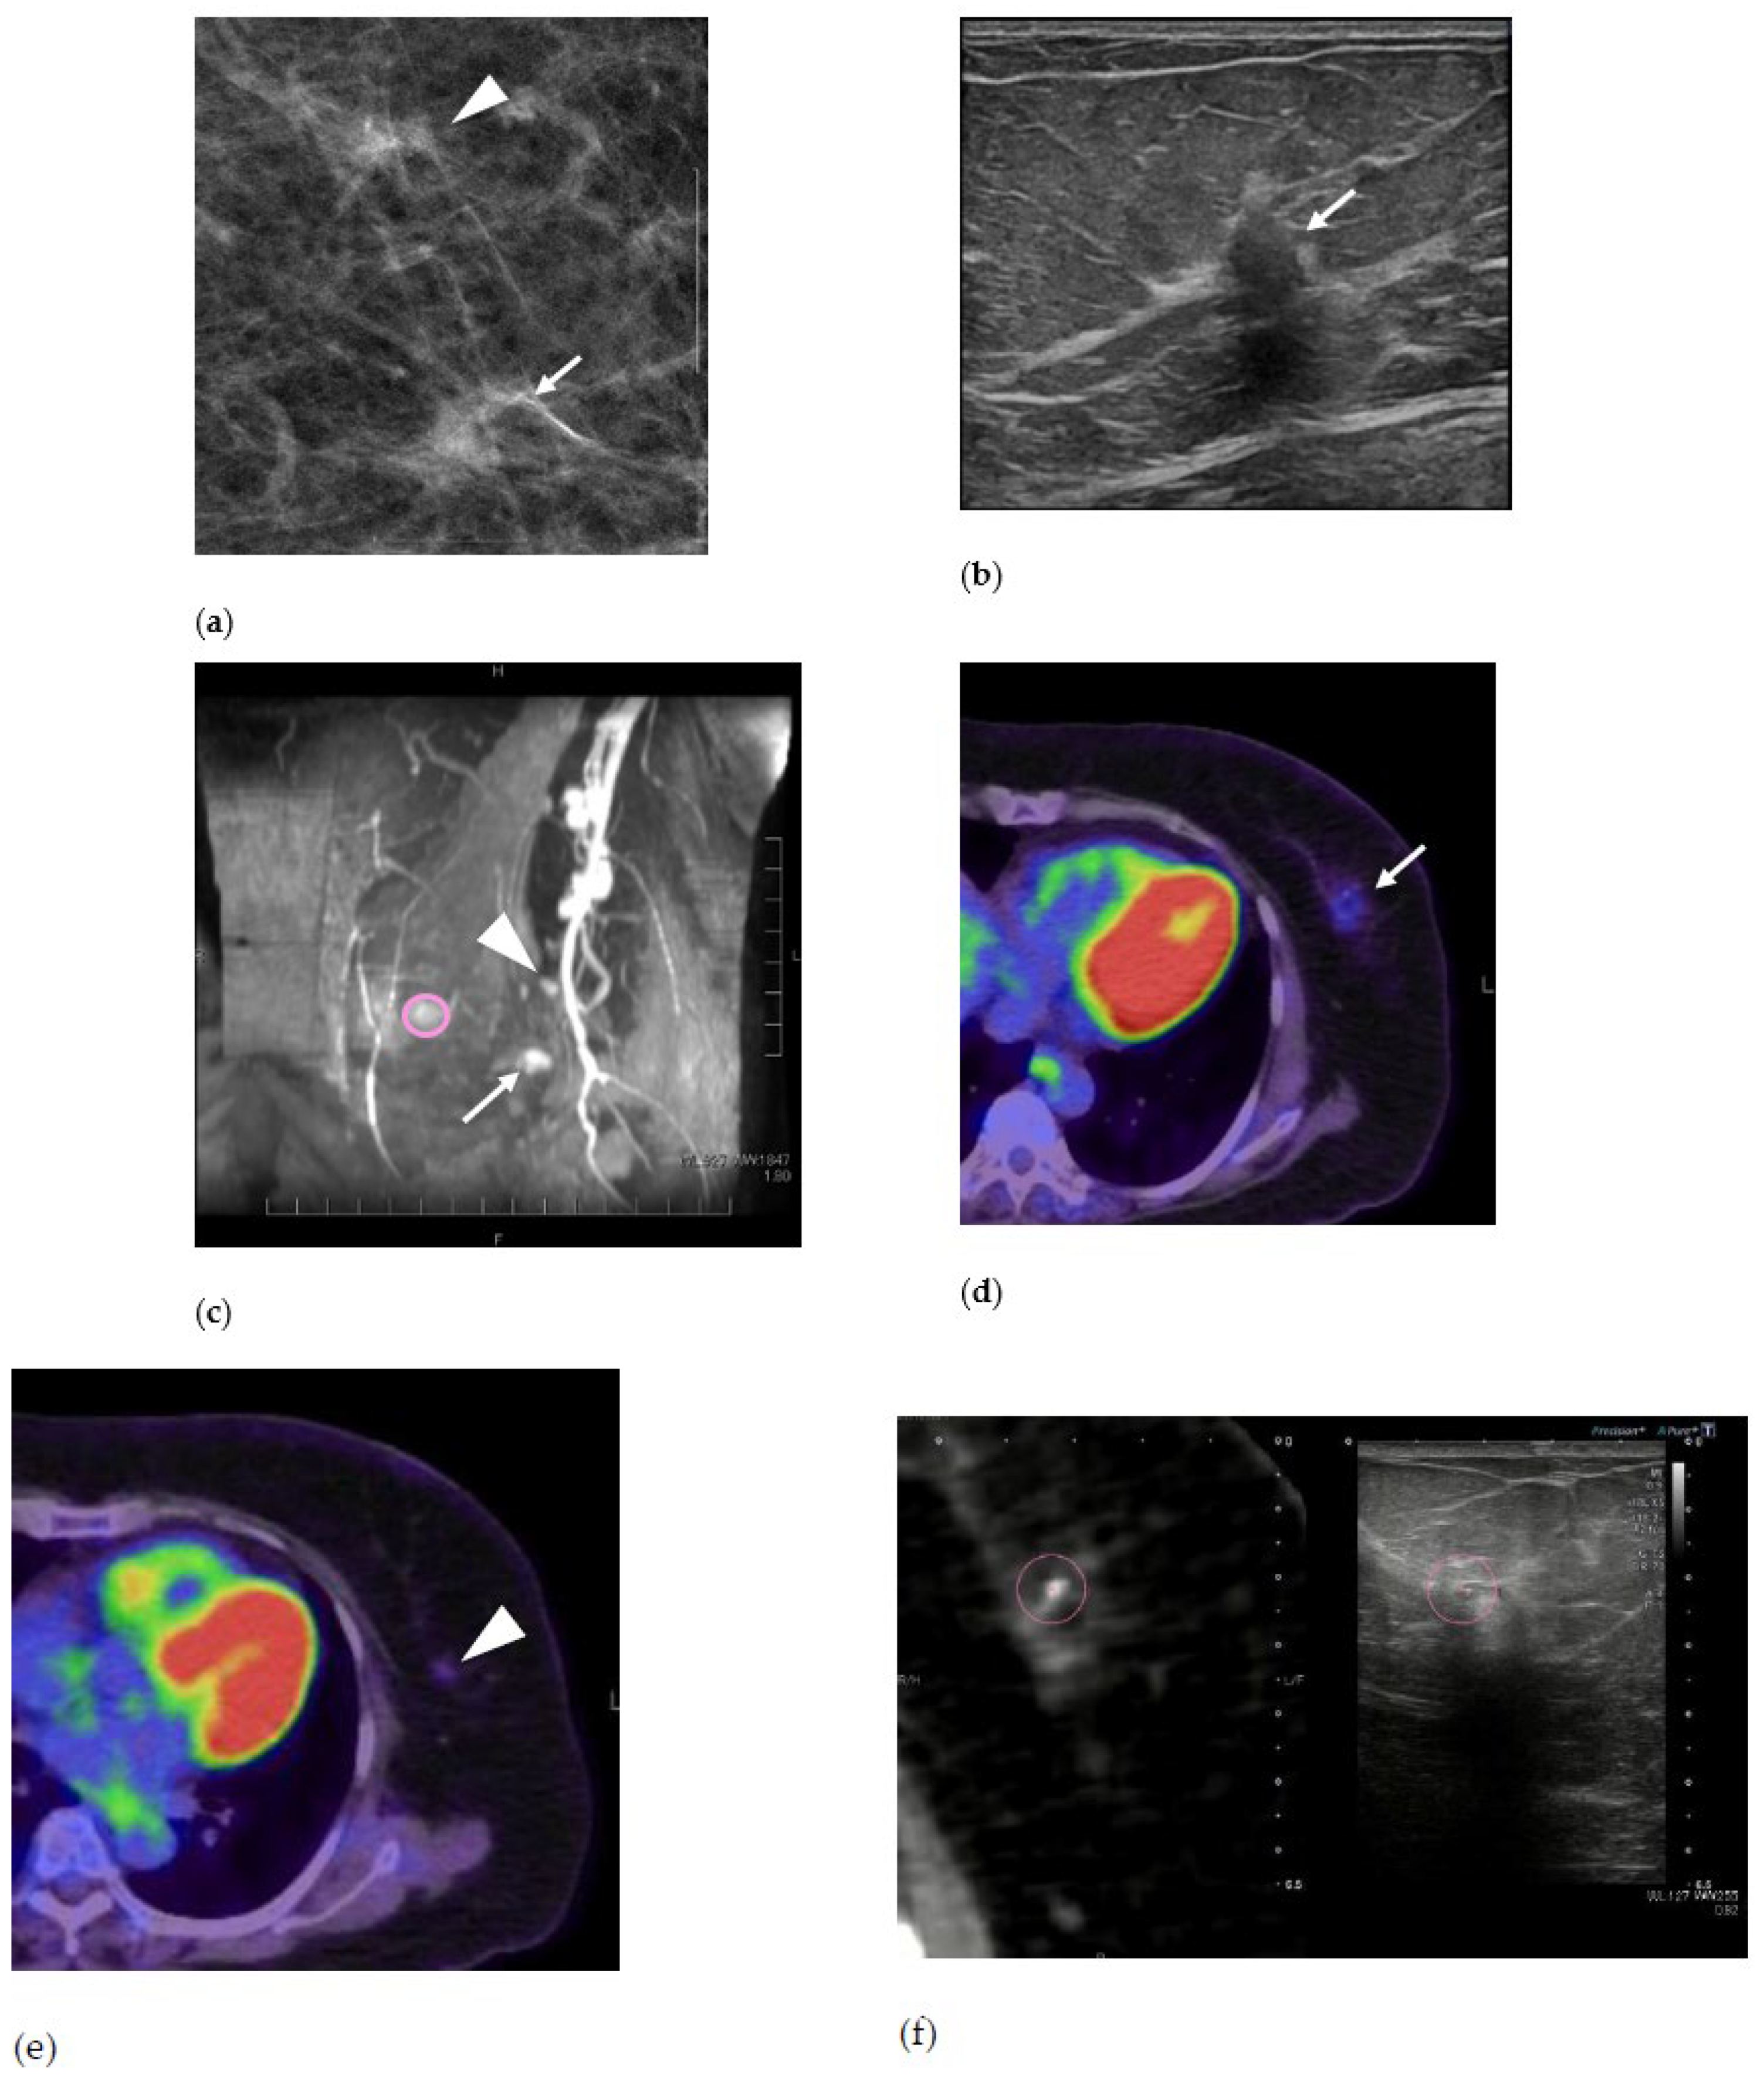

2. Case Presentation